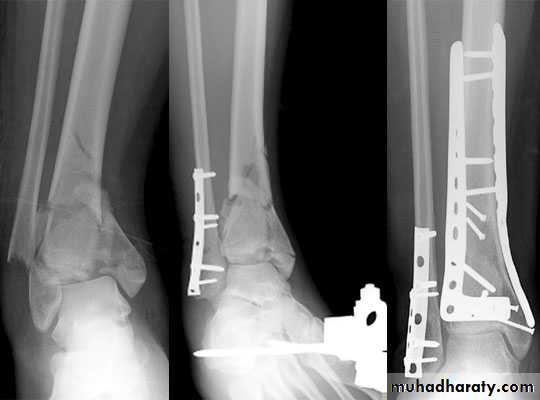

For displaced fractures and failed conservative treatment, open reduction and internal fixation is mandatory by malleolar screws, plate and screws.

Pilon fractures ( comminuted fracture of tibial plafond)

Patients give history of fall from height (axial compression), followed by severe swelling, bruises and fracture blisters . X ray and CT scan are needed to study the fracture details.Treatment: control soft tissue swelling(elevation and external fixation) for 2-3 weeks then open reduction and internal fixation

Fixations of fractures tibia and fibula

Indicated mainly when the fracture cannot be reduced adequately by manipulation, or when plaster alone fails to maintain an acceptable position of the fragments.Closed intramedullary nail or Plate and screws used commonly.